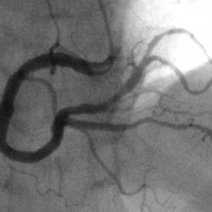

- 章2管影概怎样移动影机有目的性地影如何做冠影从AP位开始右前斜和正位、位在LM病变时的两个view技术点如何充分暴LCX如何移开LCX充分暴LAD如何有目的地暴LAD为了